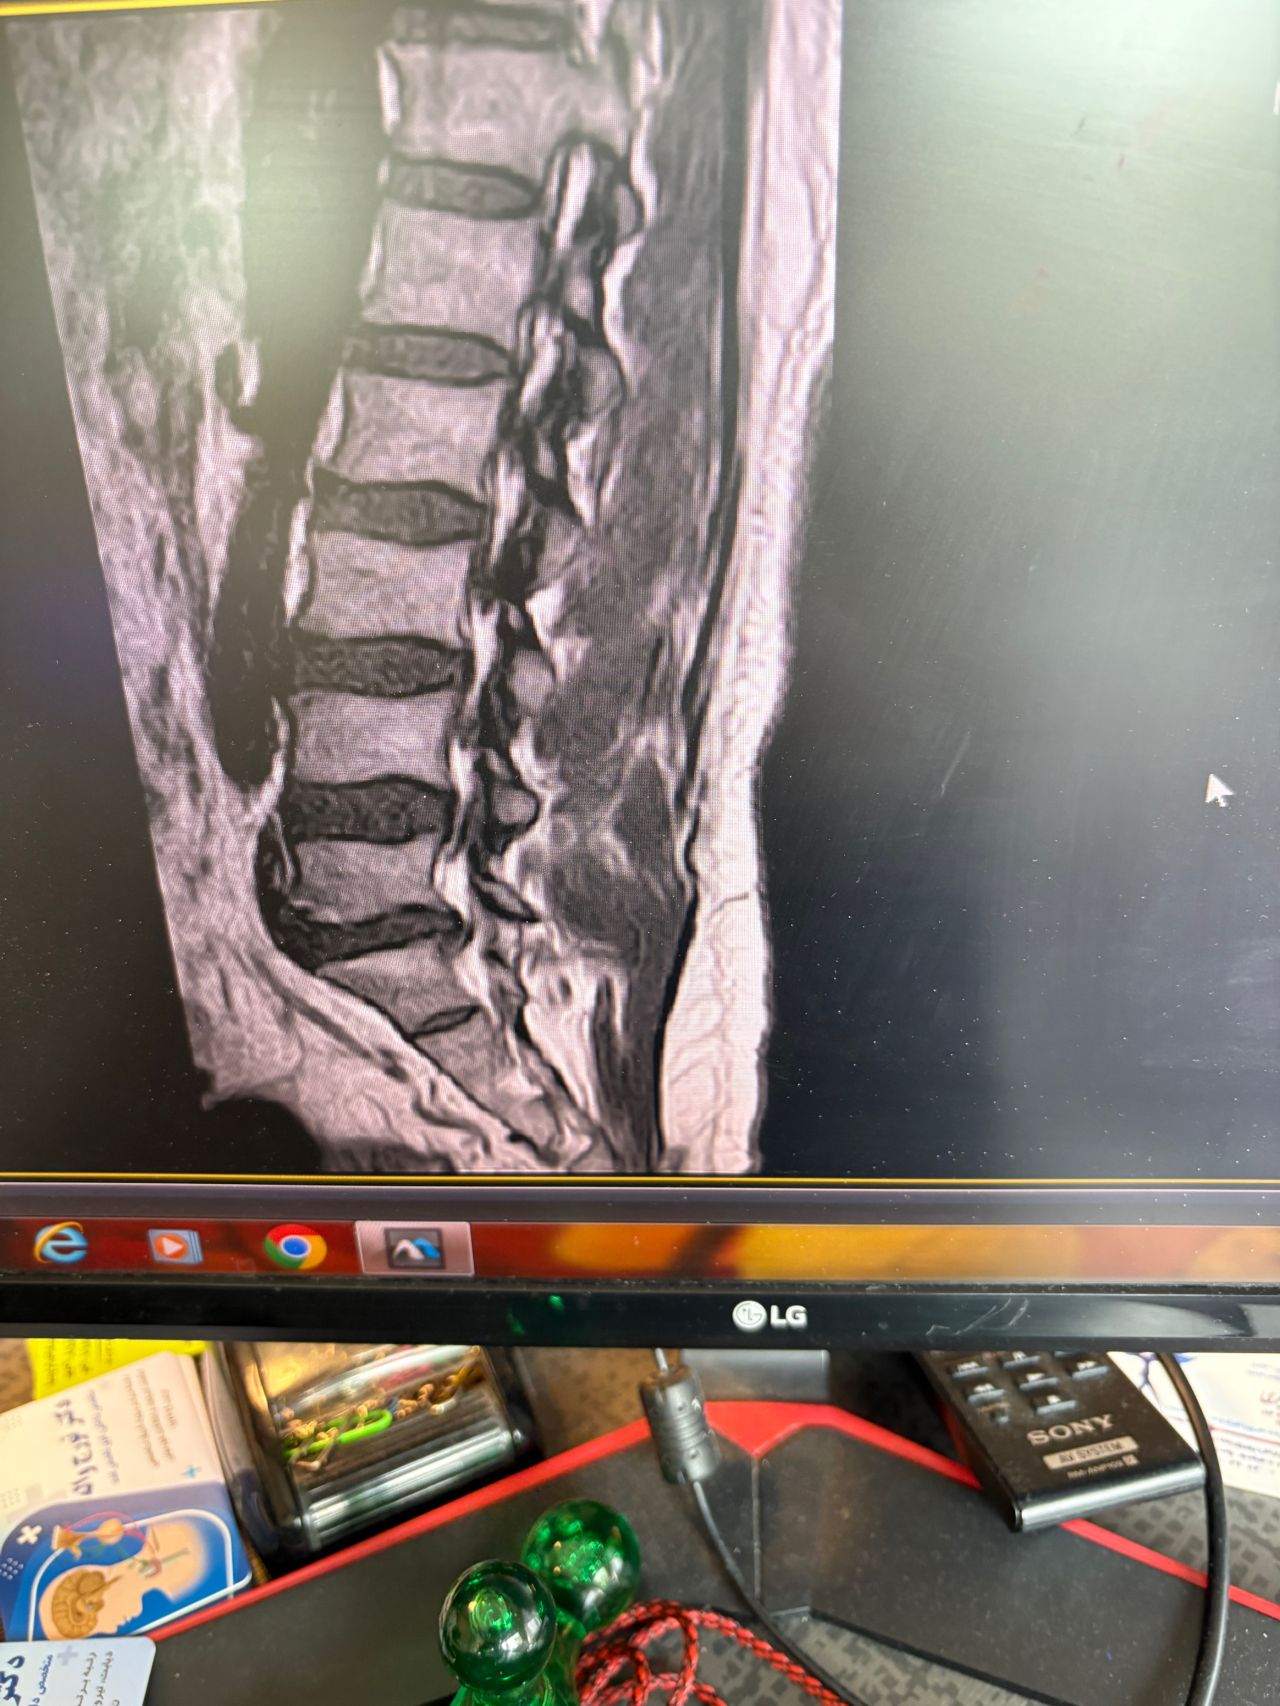

A 65-year-old patient presented to my office 20 days ago with right hip/gluteal pain, mainly occurring after walking approximately 200 meters. He also reported right shoulder and neck pain.

On examination, the right shoulder range of motion was normal. However, cervical spine (C/S) range of motion was severely restricted by about 80% in all directions. There was severe right C5–C7 dysfunction. Neurological examination revealed a positive right-sided Hoffman’s sign, unremarkable Babinski sign, and bilateral L4 deep tendon reflexes graded 1+. On palpation of the lumbar spine, step defects were noted. Right hip examination was otherwise normal.

Cervical and lumbar MRI, dynamic lumbosacral X-rays, and EMG/NCV of the lower limbs were ordered. The patient brought all results today (August 18, 2025).

Request:

Please review his MRI and X-ray findings. Based on these, what are your differential diagnoses, final diagnosis, and plan of management (POM)?